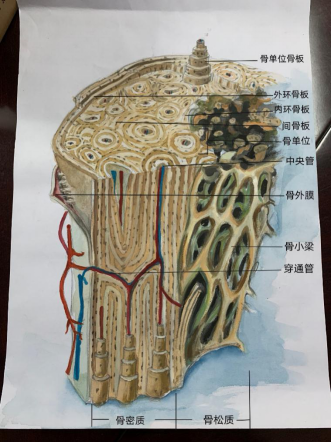

二等奖作品(4):长骨骨干立体模式图 作者:19临床医学 林子龙